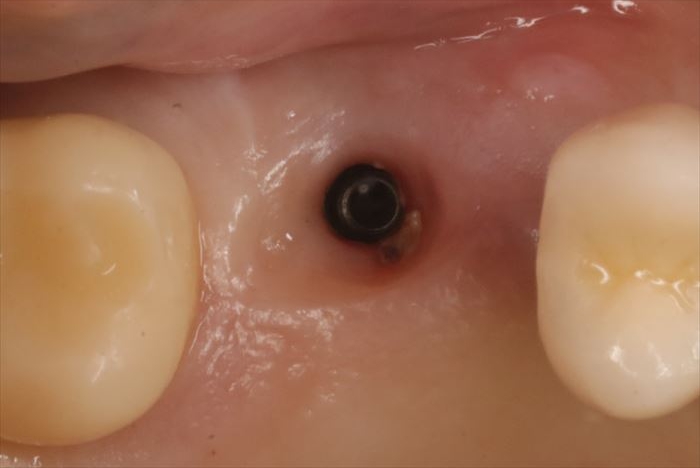

咬合面のスクリューを緩め、まずは被せ物(クラウン)を取り外しました。

インプラント本体が理想的な位置よりも頬側に存在していることがわかります。

インプラントが理想的な位置よりも頬側に位置していることがわかります。

アバットメント(中継ぎパーツ)を取り外しました。